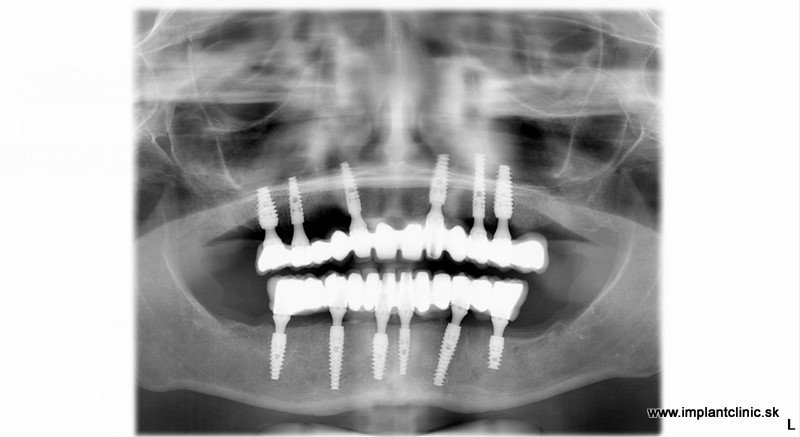

Vrchná čeľusť : 5 extrakcií, 6 zubných implantátov, 12 – členný keramický mostík

Spodná čeľusť: 11 extrakcií 6 zubných implantátov 12 – členný keramický mostík

V prípade našej pacientky Jany sa po extrakciách začalo implantovať do oboch čeľustí. MUDr. Salka zaviedol spolu 12 zubných implantátov. Celé ošetrenie v tomto prípade trvalo 5 hodín. Je to maximálny počet hodín na ošetrenie v ambulantnej celkovej narkóze.